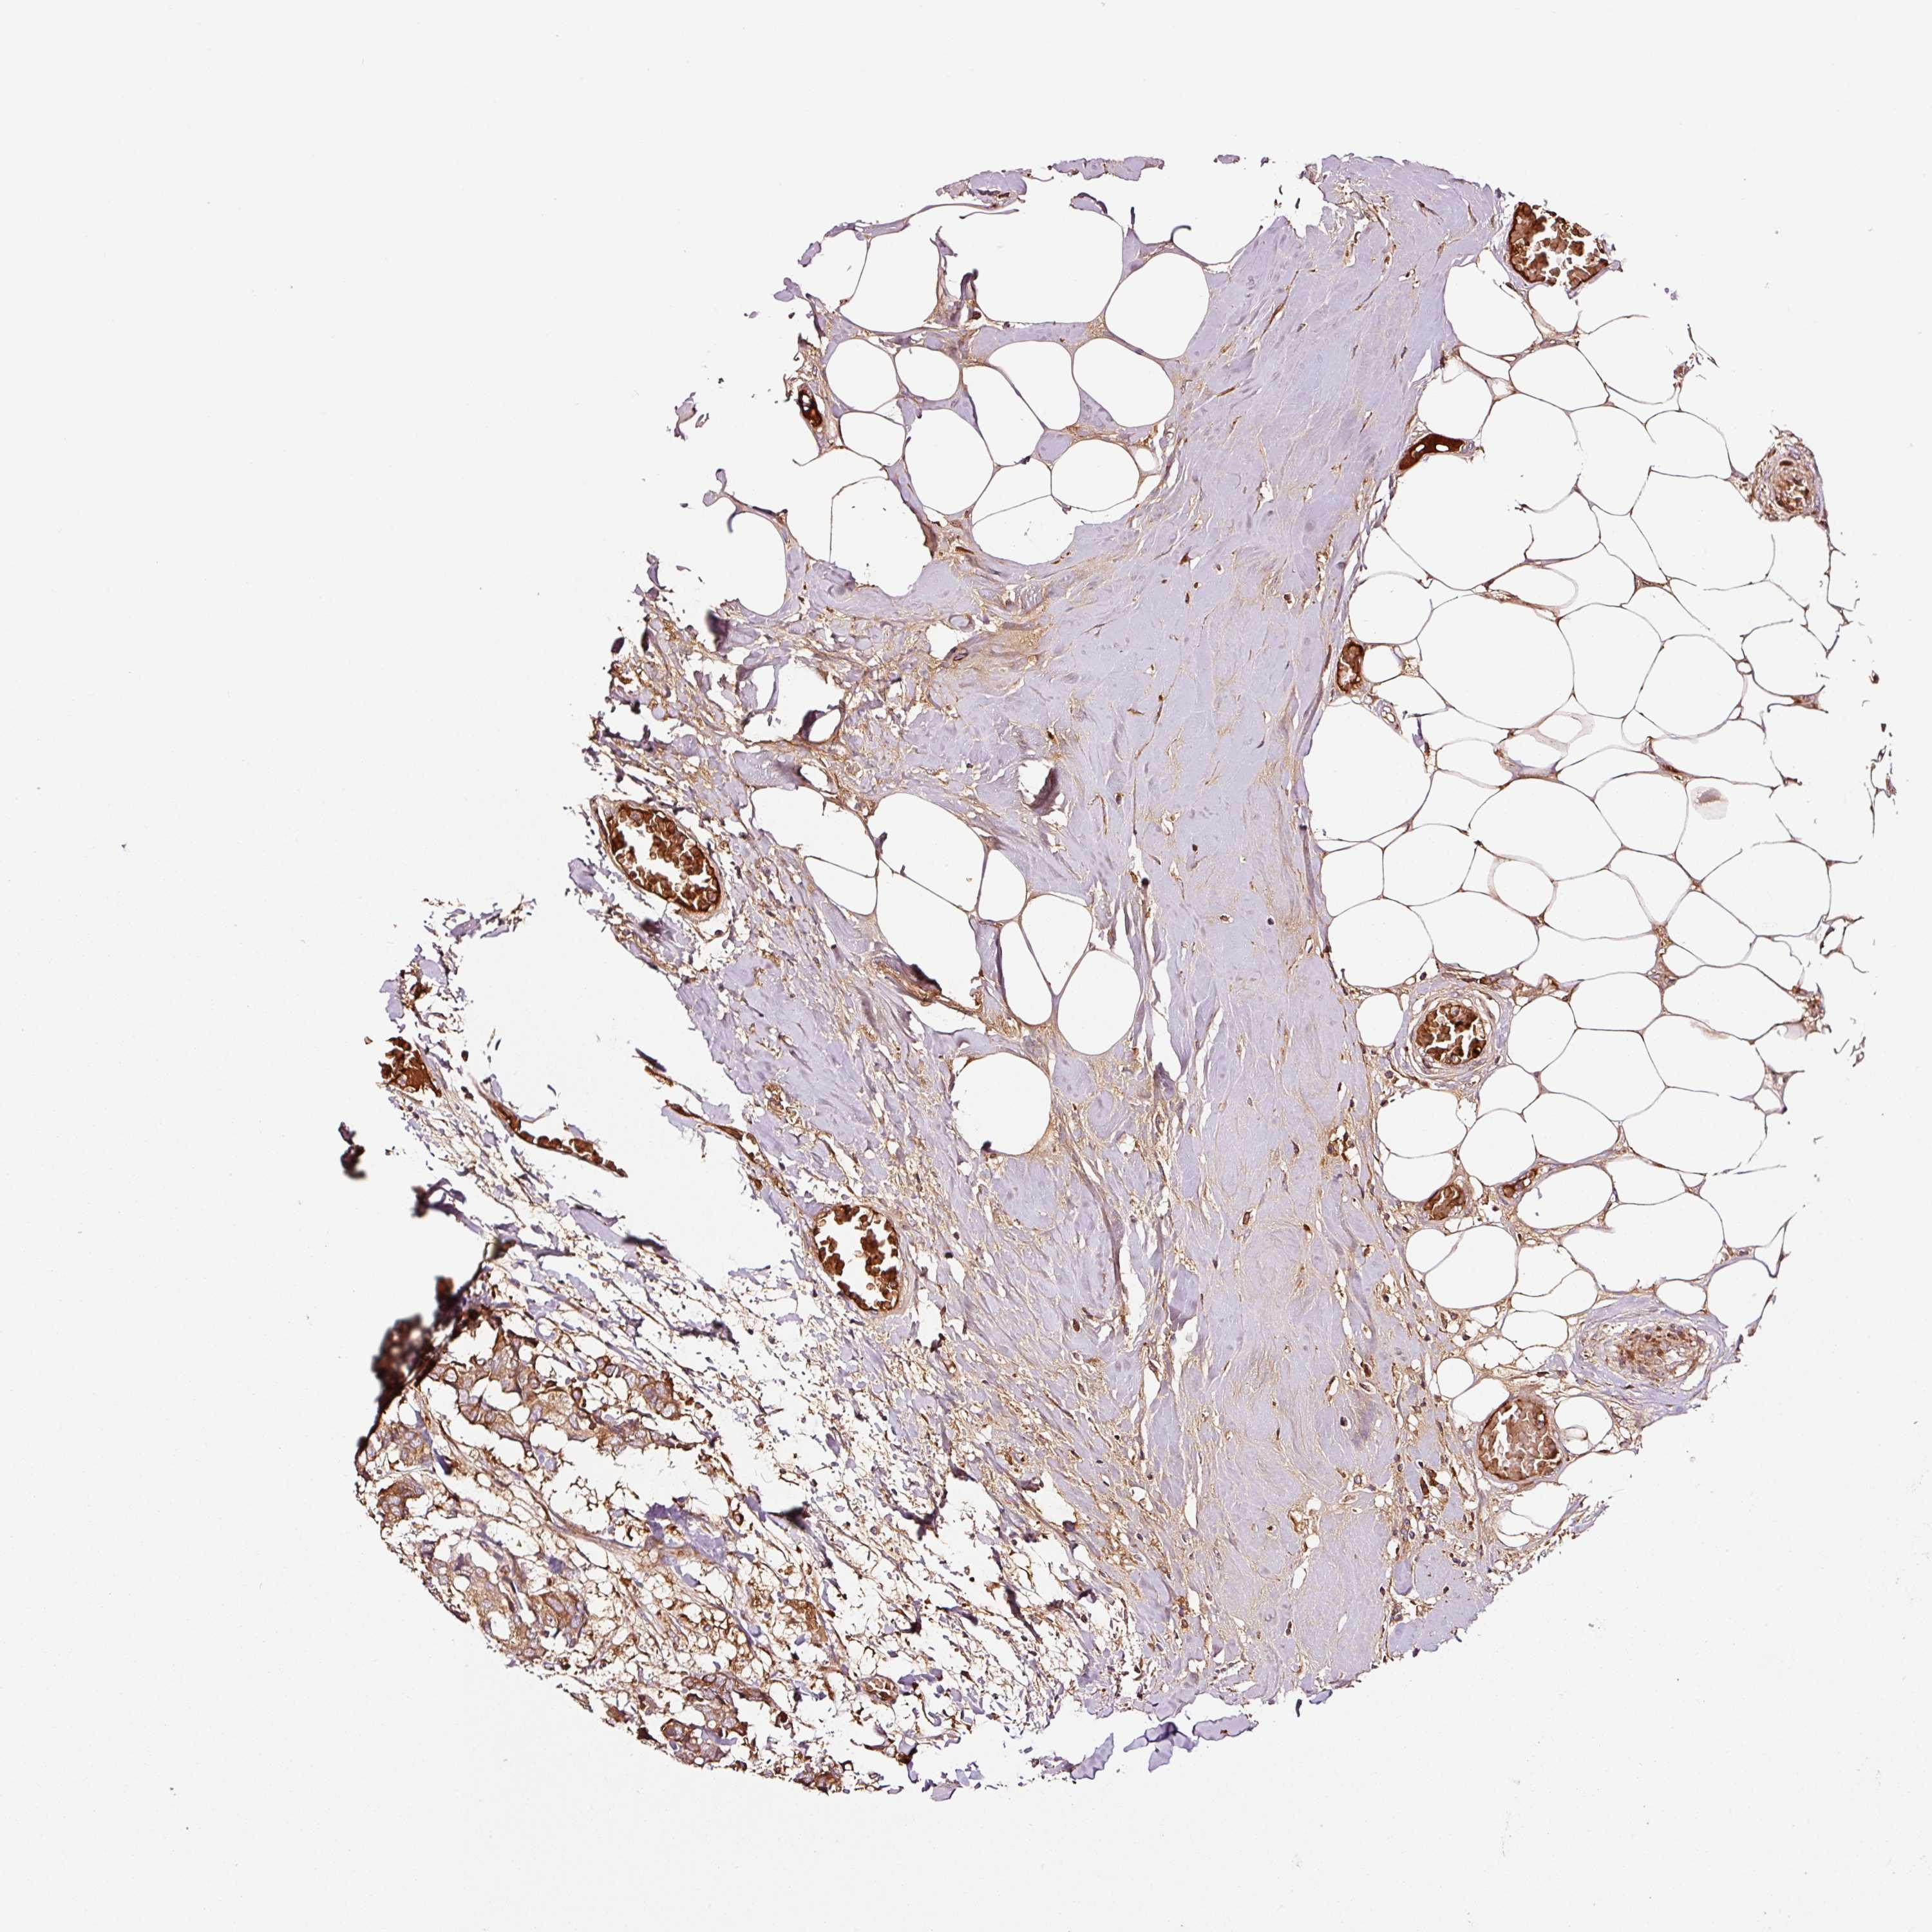

BRCA TCGA BRCA VALIDATION PROTEIN EXPRESSION

ANTIBODIES

AND

VALIDATION